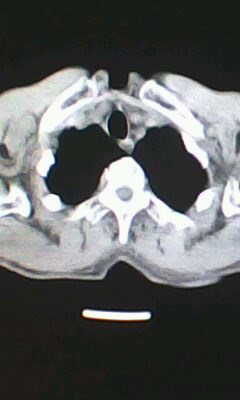

胸廓呈桶状,双膈低平,肺实质及纵隔未见明显异常密度灶考虑肺气肿.

肺气肿

以下是引用ctkz987在2010-5-5 21:30:00的发言:[br]胸廓呈桶状,双膈低平,肺实质及纵隔未见明显异常密度灶考虑肺气肿.

弥漫性肺气肿 但内胆管轻度扩张

临床诊断:copd